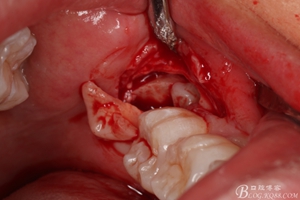

圖12.高速牙鉆分牙

圖13. 分開的38牙冠和牙根

圖14. 分別取出38分開的牙冠